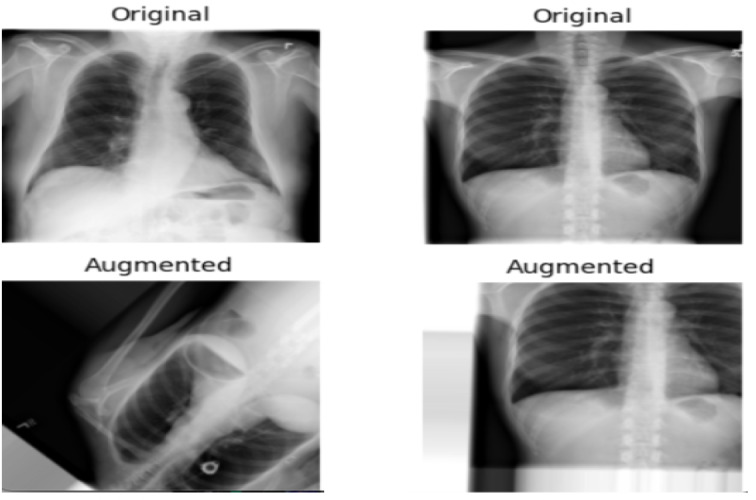

Objective: This study aimed to evaluate the performance of 6 convolutional neural network architectures-Visual Geometry Group-16 (VGG16), VGG19, Residual Network-50 (ResNet50), ResNet101, ResNet152, and Inception-ResNet-V2-in classifying chest x-ray (CXR) images as either normal or TB-positive. The impact of data augmentation on model performance, training times, and parameter counts was also assessed.

Methods: The dataset of 4200 CXR images, comprising 700 labeled as TB-positive and 3500 as normal cases, was used to train and test the models. Evaluation metrics included accuracy, precision, recall, F1-score, and area under the receiver operating characteristic curve. The computational efficiency of each model was analyzed by comparing training times and parameter counts.

Results: VGG16 outperformed the other architectures, achieving an accuracy of 99.4%, precision of 97.9%, recall of 98.6%, F1-score of 98.3%, and area under the receiver operating characteristic curve of 98.25%. This superior performance is significant because it demonstrates that a simpler model can deliver exceptional diagnostic accuracy while requiring fewer computational resources. Surprisingly, data augmentation did not improve performance, suggesting that the original dataset's diversity was sufficient. Models with large numbers of parameters, such as ResNet152 and Inception-ResNet-V2, required longer training times without yielding proportionally better performance.